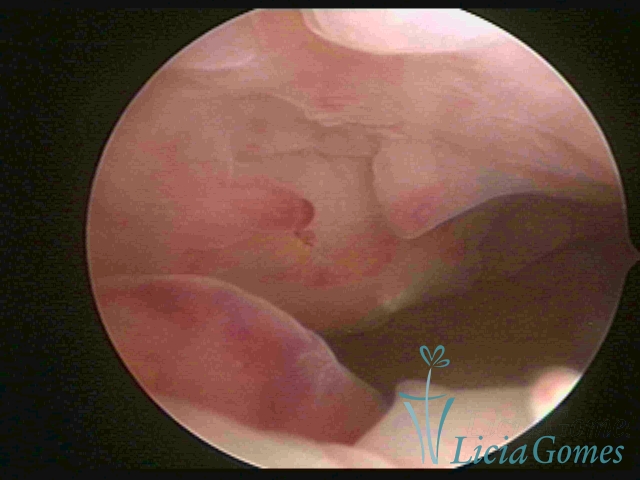

Polypoid hypertrophy is viewed when the endometrial growth is more pronounced and, since the space of the uterine cavity is limited, it presents the formation of folds or grooves, simulating pseudopolypoid or polypoid lesions.

In simple hypertrophy, there is an increase in the endometrial thickness with a protuberance of the glandular punctuate, differing from the proliferative endometrial pattern by the loss of superficial reticular vascularization. Another form of simple hyperplasia is the cystic glandular hyperplasia, which also presents cystic lesions intercalated to the hypertrophic endometrium.

Complex Hyperplasia has a pseudopolypoid aspect which resembles cerebroid tissue or with decidual reaction. The superficial vascularization is more evident, presenting vessels in the shape of corkscrew or spiral.

Atypical hyperplasia and histeroscopical aspect are similar to complex hypertrophy, also presenting vascularization with atypias. With the increase of the thickness of the superficial vessels, tissues in necrosis may also be found.